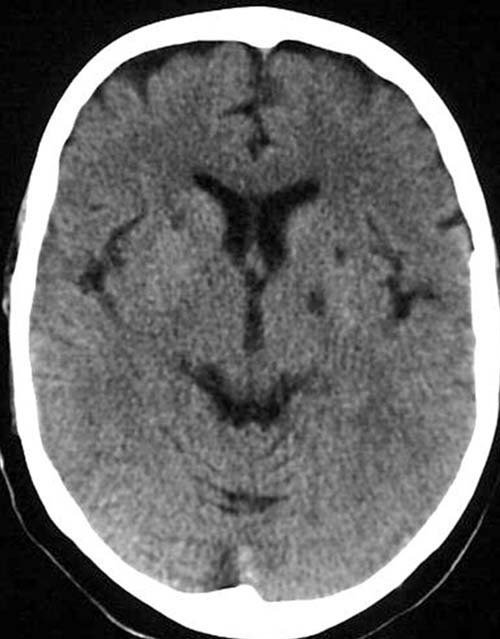

CCT nativ (ohne Kontrastmittel).

Hypodense (liquorisodense) Areale in den Stammganglien.

Alte lakunäre Infarkte (> 3 Monate).